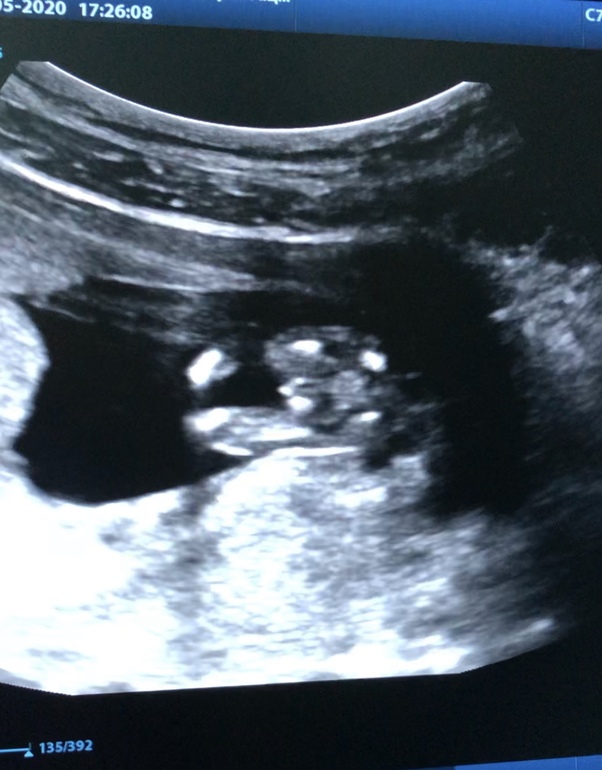

Вопросы про УЗИ, обследования и анализы: что, где, как, когда?Впервые пишу в это сообщество!) прошла несколько дней назад 1 скрининг на сроке 12.5 недель)) все по результатам хорошо, предположили пол -сказали похож на мальчика) хотела спросить, может кто разбирается либо опытные многодетные мамочки у которых есть тоже фото на таком сроке, как думаете на кого больше похож ? Я почему в мальчике не уверена

13 недель ровно. Врач сказала что девочка. Специально развернула этим местом и сфотала.

По-моему, мальчик. Весьма так явно орган торчит:)) Но у друзей «100% мальчик» после 20 недель неожиданно трансформировался в девочку. Так что все бывает.

Как то на мальчика больше похож,у девочек то тоже может торчать половой бугорок но мне кажется не настолько

У меня пять мальчиков. Ракурс шикарный. Обычно такое фото делают для тех, кто сомневается. Мальчик у Вас 120%